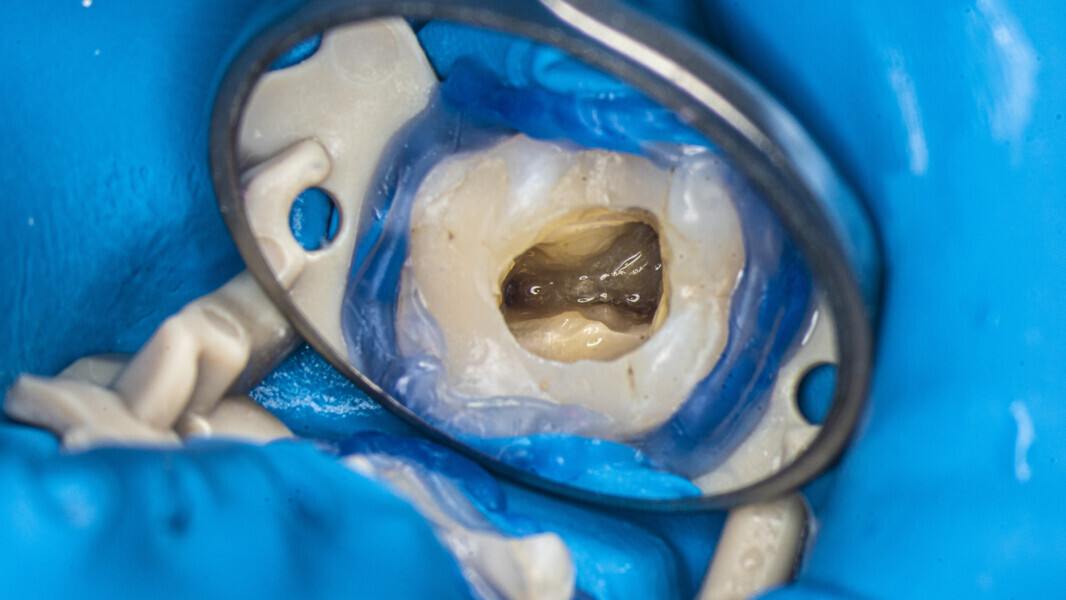

An access cavity had already been created by the referring dentist. During visualisation of the pulp chamber (Fig. 22), remnants of the pulp were identified. In order to properly identify canal orifices, cleaning of the pulp chamber was necessary. This is standard protocol for every endodontic treatment, and it is very important in order not to transport debris from the pulp chamber to canal space. This procedure was done using an Er,Cr:YSGG laser with a wavelength of 2,780 nm (Waterlase, BIOLASE) and RFPT5-10 tip (Fig. 23). After this procedure, which should be done according to the protocol of 1 minute of continuous activation and 1 minute of rest (Fig. 24), the operator can start the instrumentation protocol.

Fig. 22